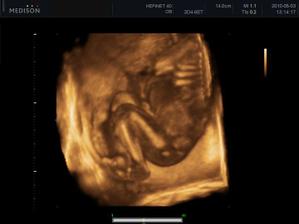

Náš zázrak